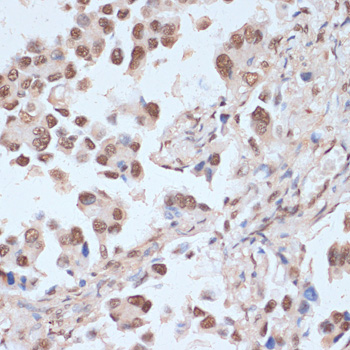

AMP-activated protein kinase (AMPK), an important serine/threonine protein kinase that plays a key role in coordinating metabolism and energy. It is the core to studying diabetes and other metabolic diseases. AMPK is expressed in a variety of metabolic-related organs and can be activated by various stimuli including cellular stress, exercise, and many hormones and substances that affect cell metabolism. AMPK proteins from different species all exist in the form of a heterotrimer complex consisting of an α-catalytic subunit, a β-regulatory subunit, and a γ-regulatory subunit.